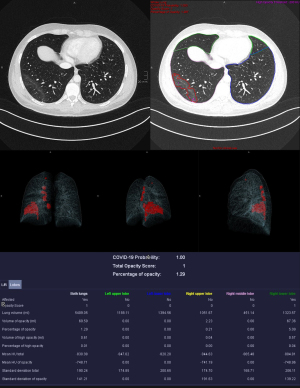

Manual corrections were made after the automatic analysis was completed. Lung lobes were examined and adjusted accordingly. Extensive corrections were required in patients with soft tissue emphysema, where air was confused with lung tissue, and in patients with pleural effusion. Discrepancies between vessel markings and consolidations due to contrast agent were also corrected. Motion artifacts and foreign bodies such as stents and clips were identified, and artifacts appearing as ground-glass opacities or consolidations were removed from the analysis as far as possible. Examples were given in Figures 3,4.

Quantitative CT analysis

The mean probability of COVID-19 in deceased patients was not significantly different (P=0.22) compared to patients that survived, but volume of opacity and high opacity were significantly higher (P=0.007 and 0.04) in deceased patients (Figures 5,6).